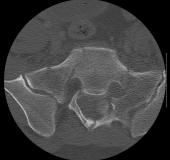

X-Rays and scans of the damaged right & left legs plus the pelvis

These x-rays were taken just after the accident. Some of the bones on the right leg have already been pushed back into the leg. The CT

scans show various views of the ankles and pelvis prior to any corrective surgery. Fibula bracing is clear in some of the images as well as

bracing that was used to secure the "open book" pelvis. In some of the last images it is apparent that the upper part of Liam’s left fibula is

broken. Liam was told that the pain he felt was most likely a muscle cramp. Nothing was done to repair this break and you will see in further

x-rays that the bone shifted and later fused in such a way as to add to the reduction of Liam’s leg length. The last photo shows the stint

used to block any potential blood clots from moving up.